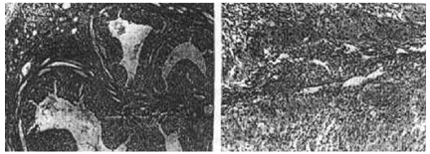

Как видно из данных, приведённых в таблице 2,у 34,5% больных наблюдалась гиперплазия и лютеинизация гранулезы и/или тека-клеток кистозно- атрезирующихся фолликулов (рис.1А). На этом фоне весьма часто (у 39,7% пациенток) развивался очаговый текоматоз (рис.1Б,В). Кроме того, в 32,9% случаев наблюдалась также очаговая стромальная

А Б

В Г

Д Е

Рис.1. А. Гиперплазия лютеинизация гранулезы и/ или тека-клеток кистозно-атрезирующихся фолликулов; Б. Очаговый текоматоз с лютеинизацией; В. Накопление липидов в тека-лютеиновых клетках; Г. Очаговая стромальная гиперплазия; Д. Кисты жёлтого тела; Е. Пролиферация тека-лютеиновых клеток жёлтого тела в репродуктивном возрасте.

Рис.2 А. Аденофиброма с функционирующей стромои; Б. Аденофиброма с нефункционирующей стромой.

гиперплазия (рис.1Г). Частой находкой оказались кисты жёлтого тела (38,2%), а также пролиферация тека-лютеиновых клеток жёлтого тела (рис.1Д,Е).

Следовательно, имеющаяся картина анатомической перестройки яичников и представляет собой тот морфологический субстрат, который является ответственным за усиленную секрецию эстрогенов и прогестерона. Опухоли и опухолеподобные процес-сы (серозная цистаденома, аденофиброма и эндометриоз) яичников в репродуктивном возрасте встреча-лись редко. Из числа указанных опухолей яичников, гормонально-активной является аденофиброма с функционирующей стромой (рис.2).